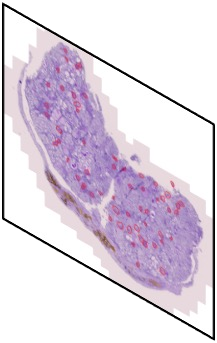

In digital pathology, the traditional method for deep learning-based image segmentation typically involves a two-stage process: initially segmenting high-resolution whole slide images (WSI) into smaller patches (e.g., 256x256, 512x512, 1024x1024) and subsequently reconstructing them to their original scale. This method often struggles to capture the complex details and vast scope of WSIs. In this paper, we propose the holistic histopathology (HoloHisto) segmentation method to achieve end-to-end segmentation on gigapixel WSIs, whose maximum resolution is above 80,000$\times$70,000 pixels. HoloHisto fundamentally shifts the paradigm of WSI segmentation to an end-to-end learning fashion with 1) a large (4K) resolution base patch for elevated visual information inclusion and efficient processing, and 2) a novel sequential tokenization mechanism to properly model the contextual relationships and efficiently model the rich information from the 4K input. To our best knowledge, HoloHisto presents the first holistic approach for gigapixel resolution WSI segmentation, supporting direct I/O of complete WSI and their corresponding gigapixel masks. Under the HoloHisto platform, we unveil a random 4K sampler that transcends ultra-high resolution, delivering 31 and 10 times more pixels than standard 2D and 3D patches, respectively, for advancing computational capabilities. To facilitate efficient 4K resolution dense prediction, we leverage sequential tokenization, utilizing a pre-trained image tokenizer to group image features into a discrete token grid. To assess the performance, our team curated a new kidney pathology image segmentation (KPIs) dataset with WSI-level glomeruli segmentation from whole mouse kidneys. From the results, HoloHisto-4K delivers remarkable performance gains over previous state-of-the-art models.